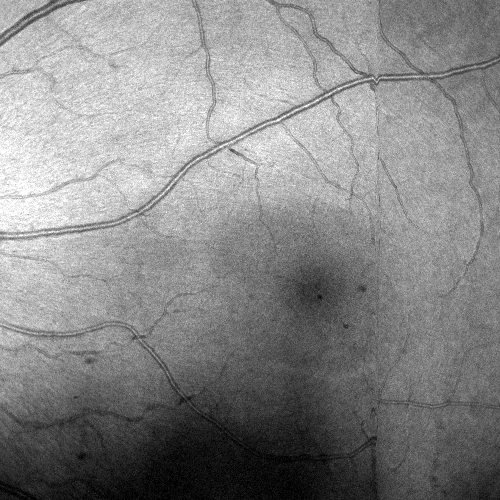

Images and estimated displacements are shown for a representative scan in Figureย 3. Tiny discontinuities prove absence of overregularization, and consistent transverse vibration indicates partial correction of ocular tremor. For quantitative analysis, we computed the median distance between the aligned A-scan displacements, and the fraction of displacements with a distance above 0.5 (problematic for supersampling) and 1 pixels (misalignments). The first and last 5% of B-scans were excluded, because they might not overlap with the orthogonal data, preventing registration. As the distributions are heavily skewed, we present box plots in Figureย 4. The three outliers in each direction in the right plot originate from the same subject, which is shown in supplementary Figureย 6. It is critical to note that the parameter density (B-scan rate 205 Hz) of the hermite splines is insufficient to fully correct ocular tremor (frequency up to 100 Hzย [16]). Therefore, this aperiodic, wave-like motion (amplitude 30โฒโฒ 1.6ย ยตm on the retinaย [16]) cannot be fully corrected, and neither is fully represented in the reproducibility error. In the transverse directions, this puts a lower accuracy limit on the evaluation scheme, but it is small compared to the pixel spacing (12ย ยตm). Using an Nvidia RTX 5000 GPU, the median and maximum runtime in the test set, excluding disk I/O which is irrelevant in clinical routine, was 8.6ย s and 31.3ย s. Tableย 1 compares average runtimes of various methods. Lastly, registration of individual B-scan repeats is demonstrated on a swept-source scanner in Figureย 5.